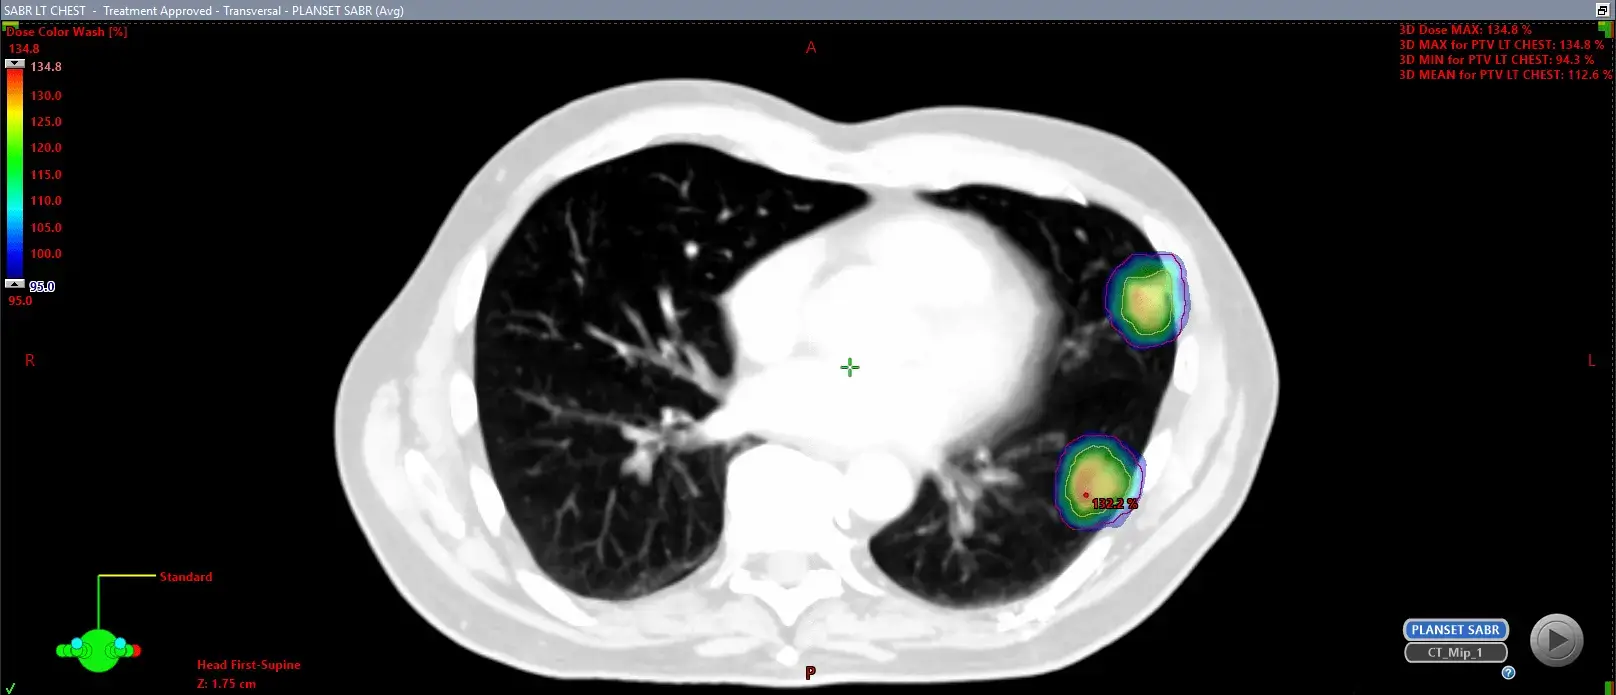

Stereotactic radiotherapy is a highly accurate form of high-dose radiotherapy, typically delivered in a limited number of sessions – usually between one and five. This treatment has a high chance of reducing or completely removing the cancerous area being targeted. The precision of the radiation dosing means that the side effects associated with SABR are generally negligible.

It is essential to acknowledge that while side effects can arise with SABR, they are generally mild and transient, causing minimal disruption to most patients’ daily routines. The frequency and severity of side effects can fluctuate based on factors such as the size and location of the tumour, the dose of radiation administered, and your individual health concerns. Common mild to moderate side effects, such as fatigue, are typically well-tolerated and manageable with supportive care measures. Before commencing treatment, I will provide you with a contact number that offers access to support and care around the clock, should you have any concerns about your symptoms.